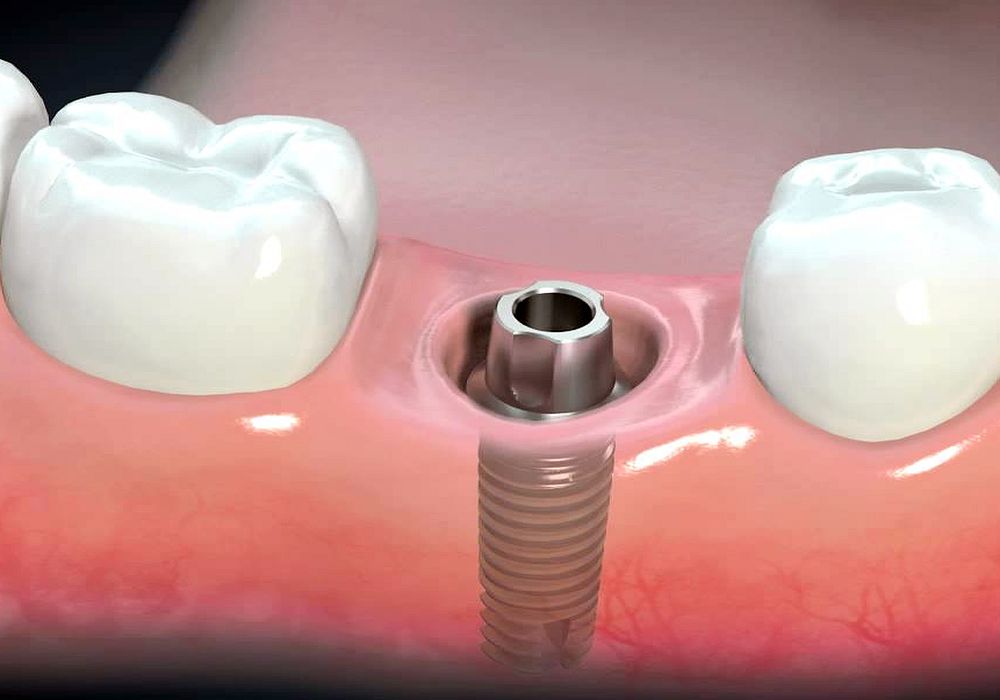

What is a Dental Implant? DDI (Dorset) Dental Implant Removal Complications Dental implant surgery can lead to a range of complications. What are the risks of getting dental implants? Learn more about potential problems that can occur in the short and long term after. The recovery time for dental implant removal depends on the case and Inappropriate and unnecessary implant therapy driven by an erroneous belief that dental implants provide enhanced. Dental Implant Removal Complications.

How Long Does Dental Implant Treatment Take? Gardens Dental Dental Implant Removal Complications Inappropriate and unnecessary implant therapy driven by an erroneous belief that dental implants provide enhanced function and esthetics over diseased or failing teeth has. Learn more about potential problems that can occur in the short and long term after. Inappropriate and unnecessary implant therapy driven by an erroneous belief that dental implants provide enhanced function and esthetics over. What are. Dental Implant Removal Complications.

Dental Implants Preston Lancashire , Replacement Teeth Implant Dentists Dental Implant Removal Complications Dental implant surgery can lead to a range of complications. In this article, we will discuss the anesthesia options available for the procedure, the recovery time after dental implant removal, and possible complications. What are the risks of getting dental implants? Inappropriate and unnecessary implant therapy driven by an erroneous belief that dental implants provide enhanced function and esthetics over. Dental Implant Removal Complications.